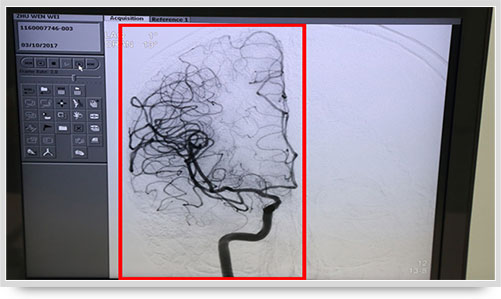

弓上造影、超選到頸內(nèi)動脈、椎動脈......在數(shù)字減影技術(shù)下,注入顯影劑后,導(dǎo)管經(jīng)患者右側(cè)股動脈在體內(nèi)推進(jìn),由于股動脈離腦血管距離較遠(yuǎn),中間“路程復(fù)雜”,對施術(shù)醫(yī)生的要求非常之高。

同時,手術(shù)臺前的液晶顯示儀屏幕上清晰地現(xiàn)顯出導(dǎo)管的路徑,在李主任的操作下準(zhǔn)確到達(dá)指定檢查部位,各條血管的“廬山真面目”清晰可見。